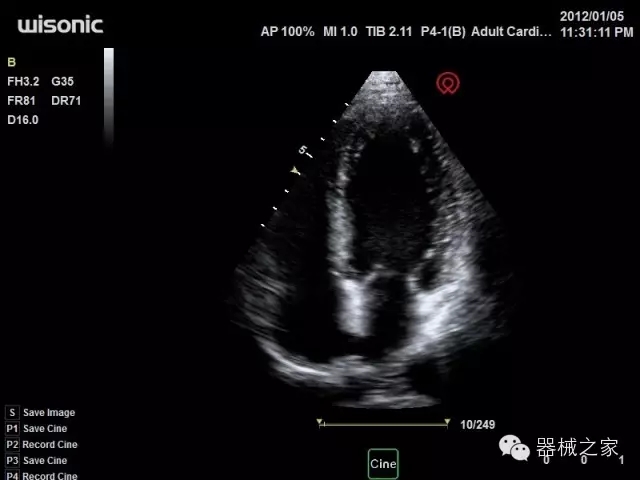

臨床圖片賞析

·心功能綜合指數(shù)(TEI指數(shù)):用于左、右心室整體心臟收縮舒張功能評估的測量方法;

·全方位可調(diào)M型:有利于更好的觀察心腔大小及室壁階段性運(yùn)動(dòng)的異常情況;

·組織多普勒成像(TDI):TDI可定量評價(jià)心肌運(yùn)動(dòng),判斷是否有局部病變,還可評價(jià)早期的舒張功能;